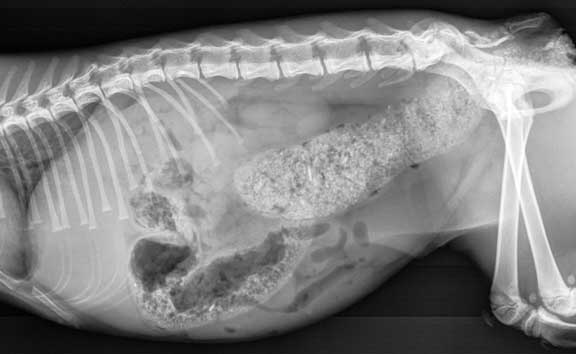

A normal cat lateral abdominal radiograph to see some of the variation. That large white granular tube is a colon filled with feces.

A normal cat lateral abdominal radiograph. Do you see the two kidneys overlapping each other?

The right kidney is more to the left, the left kidney is more to the back. Where they overlap there is a whitish area. This is called summation, and is normal.

The large intestine that is filled with feces is laying over the left kidney (the lower kidney of the two) making it hard to visualize the kidney. If we were worried about kidney disease we would give this cat an enema, or wait for it have a bowel movement, and then take another radiograph.